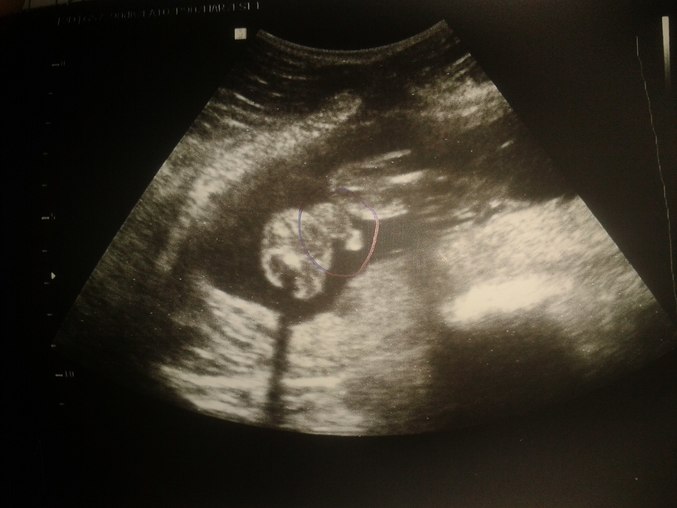

Итак, наши результаты))))

Предполагаемая дата родов по месячным 14 октября по узи 14 октября

в матке определяется 1 живой плод в головном предлежании

БПР 51 мм окружность головки 182 мм

ЛЗР 64 мм Окружность живота 162 мм

длина бедренных костей по 34,9 мм обе

Длина костей голени обе 32 мм

Длина плечевой кости по 33 мм обе

длина костей предплечий по 30 мм

компьютерный подсчет массы плода 404 г

Боковые желудочки мозга 6 мм мозжечок 20мм

Большая цистерна 5 мм

Лицо:профиль Норма носогубный треугольник Норма носовая кость 6,5мм

глазницы Норма

Позвоночник норма легкие НОРМА 0 стадия зрелости

четырехкамерный срез сердца норма с/б 140 ударов в минуту

желудок норма кишечник норма желчный пузырь норма

почки норма мочевой пузырь норма

место прикрепления пуповины к передней брюшной стенке без особенностей

Локализация плаценты задняя низкая на 15 мм выше зева

толщина плаценты 18 мм степень зрелости 0

количество околоплодных вод норма

пуповина имеет 3 сосуда Наличие гипертонуса матки Нет

Врожденные пороки развития плода: данных не обнаружено

особенности строения шейки стенок матки: без особенностей

Заключение: плод соответствует 21,1 неделям головное предлежание.Низкое прикрепление плаценты.

И у нас будет мальчик